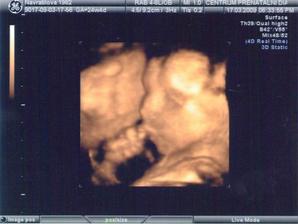

17.3. potvrzena na 3D holcicka 🙂